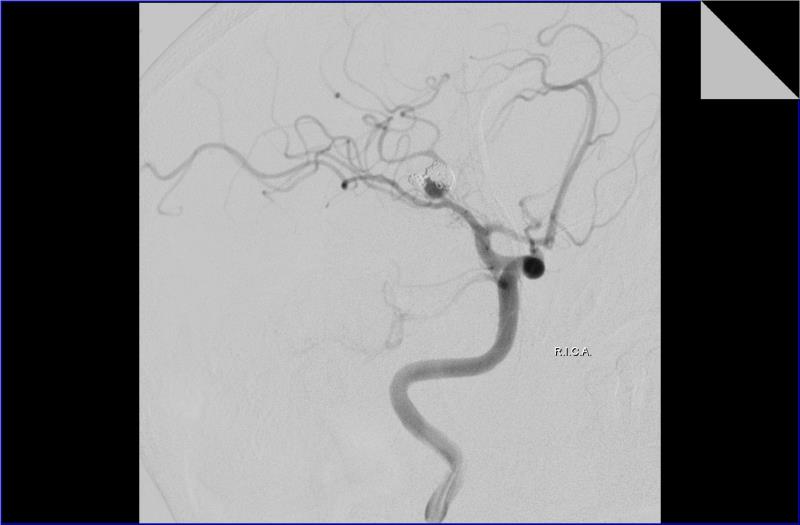

Άντρας ασθενής 55 ετών, νοσηλεύτηκε λόγω υπαραχνοειδούς αιμορραγίας και διαγνώσθηκε με ρήξη ανευρύσματος μέσης εγκεφαλικής αρτηρίας. Υποβλήθηκε σε ενδαγγειακή αντιμετώπιση με coils (εμβολισμός) και έλαβε εξιτήριο μετά την ολοκλήρωση της αγωγής του.

Πέντε μήνες αργότερα και παρά την ικανοποιητική αγγειογραφική εικόνα τόσο κατά τον εμβολισμό όσο και κατά τον επανέλεγχο στο μεσοδιάστημα, διαγνώσθηκε με νέα ρήξη του ίδιου ανευρύσματος, ενώ ο αγγειογραφικός έλεγχος κατέδειξε compaction των coil.

Στις προεγχειρητικές φωτογραφίες απεικονίζονται κατά σειρά ο αρχικός εμβολισμός, η εικόνα της επαναιμορραγίας σε αξονική τομογραφία και ο αγγειογραφικός έλεγχος μετά την επαναιμορραγία.